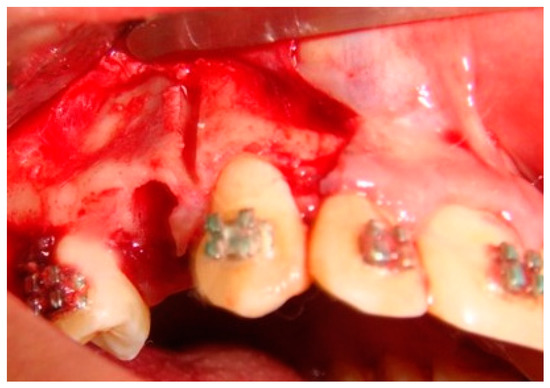

Based on the concept that teeth move faster when the resistance exerted by the surrounding cortical bone is reduced, Köle introduced a surgical procedure involving both osteotomy and corticotomy to accelerate orthodontic tooth movement [17]. Numerous studies have confirmed the usefulness of the corticotomy to accelerate orthodontic tooth movements. However, most of these studies have been conducted on animals [16,17,18,19,20]. A few studies on human subjects have also revealed the merit of this technique [21,22,23]. Therefore, an extensive review of the literature reveals that it is worth exploring the hypothesis that partial buccal corticotomy distal to the canine could enhance canine retraction and avoid the undesirable side effects of canine distraction techniques. Figure 1 offers a representation of clinical image for a better understanding of inside partial corticotomy.

Figure 1. Surgical site partial corticotomy.